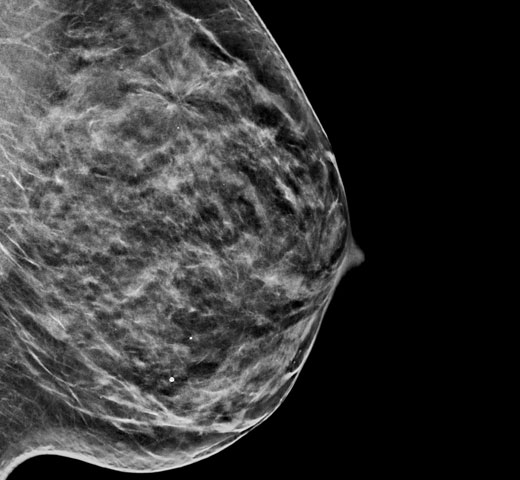

Breast Health

Hologic is transforming breast care. We apply cutting-edge science to accelerate discovery, improve efficiency and continually sharpen precision.

Breast Health Continuum of Care

Time is precious when it comes to effective detection, diagnosis and treatment of breast cancer. We strive to save you time at every step along the Continuum of Care.